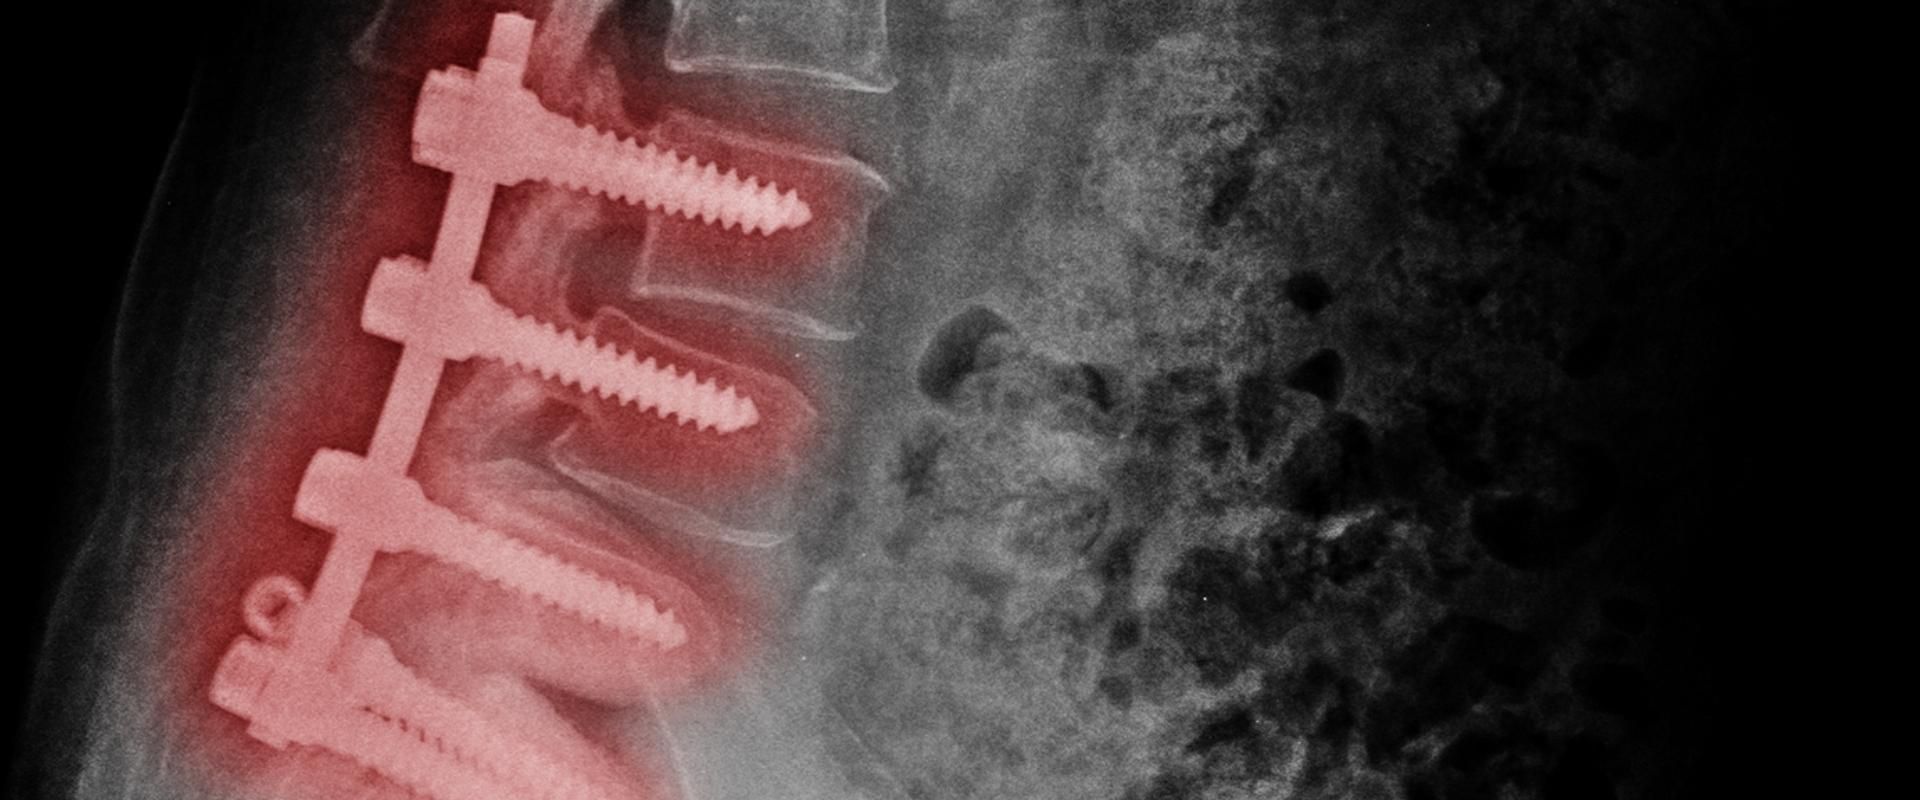

Discectomia: como funciona a Discectomia Endoscópica?

Entenda este procedimento cirúrgico para tratamento de hérnia de disco

Condições médicas que acometem a coluna vertebral, como a hérnia de disco, inicialmente...